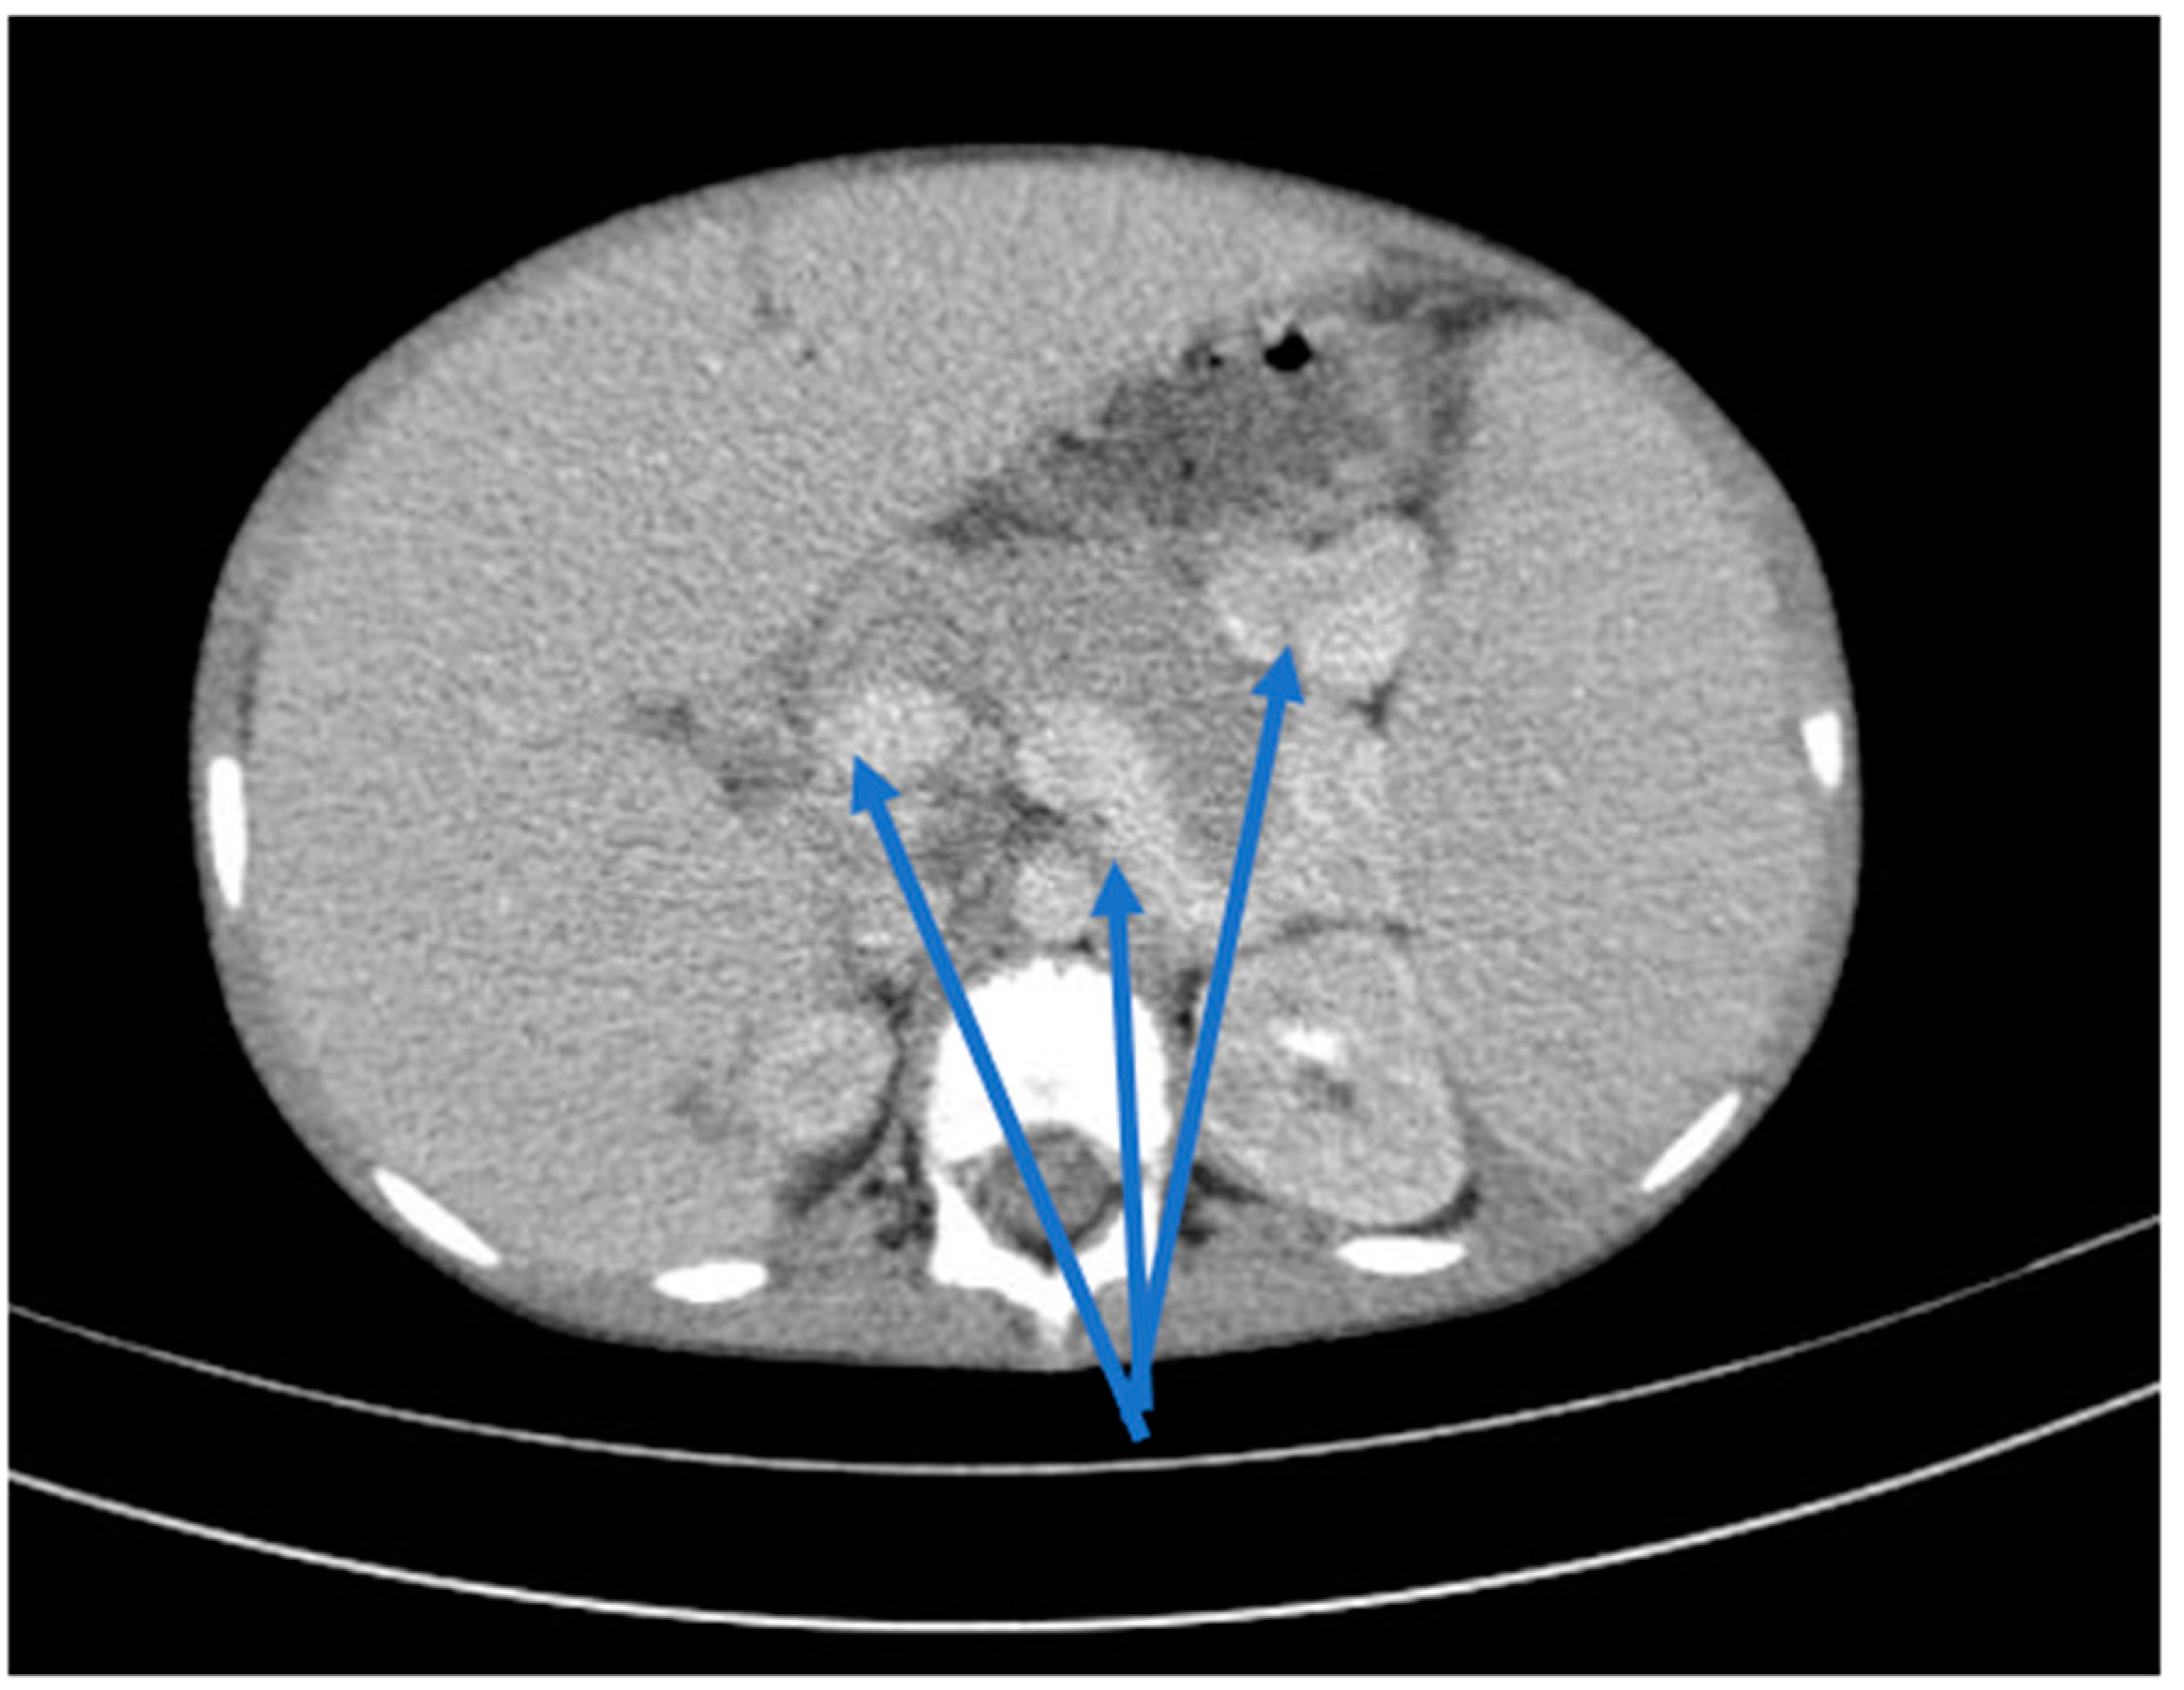

Renal function deteriorated rapidly to a creatinine clearance of 10 mL/min/1.73 m2, requiring the initiation of hemodialysis on day 5 after admission. A history of drug ingestion that could cause acute interstitial nephritis was negative. Serologic tests for Epstein–Barr virus, cytomegalovirus, hepatitis C/B, human immunodeficiency virus, Toxoplasma gondii, and tuberculin skin reaction were negative. In the absence of specific immunological findings, a marked inflammatory syndrome or antibodies such as p-ANCA, c-ANCA or antinuclear antibodies, primary immunodeficiency, a connective tissue disease or vasculitis were excluded. Renal ultrasound evaluation was highly suggestive of nephrocalcinosis. After this preliminary evaluation, the diagnosis of advanced renal disease was made; therefore, the patient started chronic hemodialysis. Thoracic–abdominal computed tomography confirmed renal medullary calcifications, hepatosplenomegaly, hyperdense splenorenal and splenogastric masses as indicators of portal hypertension (Figure 3 and Figure 4).

Figure 3.

Axial CT scans, bilateral medullary nephrocalcinosis (blue arrow).